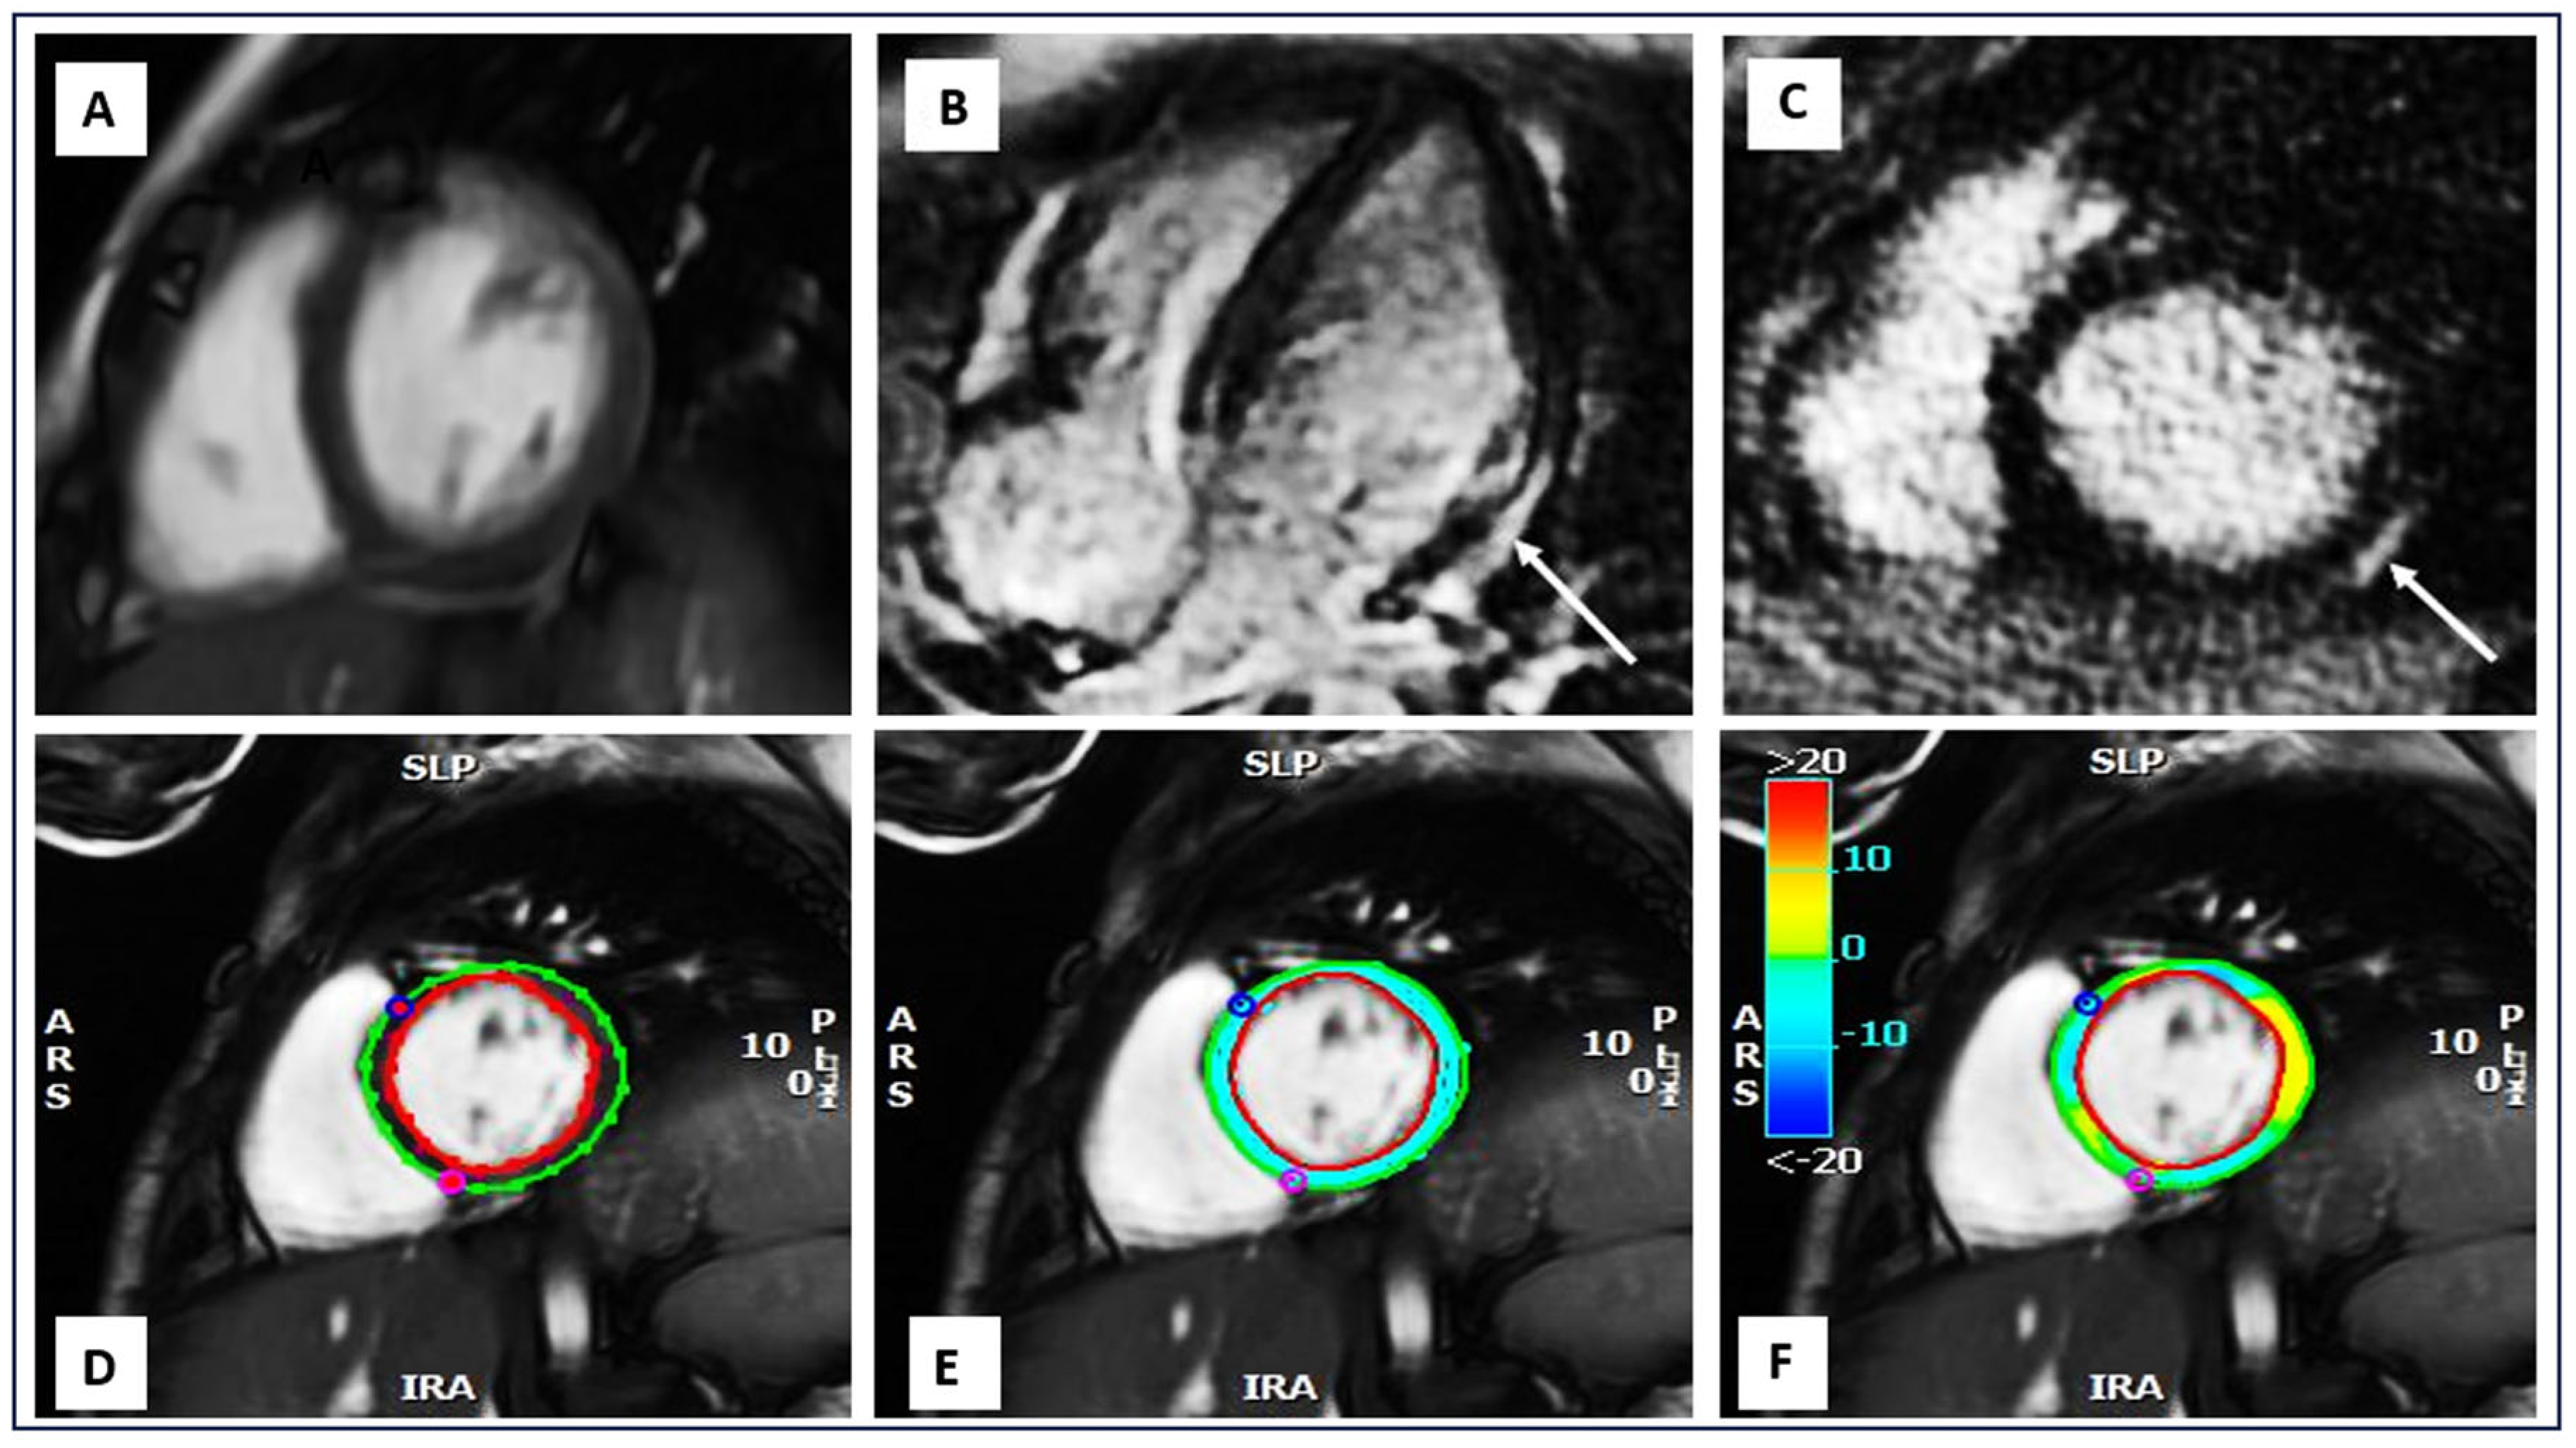

- Our research highlights the use of CMR-FT in detecting myocardial strain abnormalities in DMD patients without relying on late gadolinium enhancement (LGE).

- Benameur, N.; Mahmoudi, R.; Caiani, E.G.; Arous, Y.; Saâdaoui, F.; Mahjoubi, H. Assessment of the relationship between regional wall motion abnormality score revealed by parametric imaging and the extent of LGE with CMR. Clin. Imaging 2022, 89, 68–77. [Google Scholar] [CrossRef]